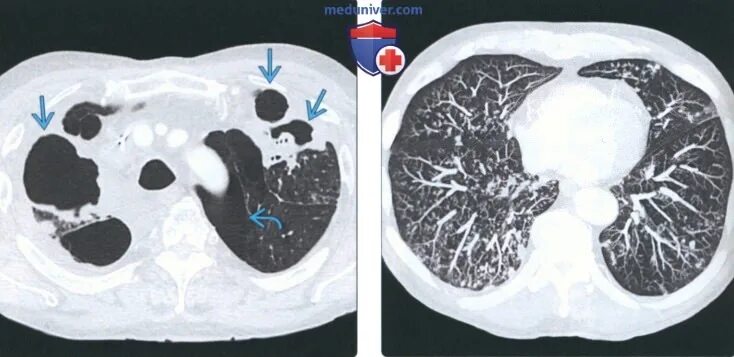

Бронхиолит причины